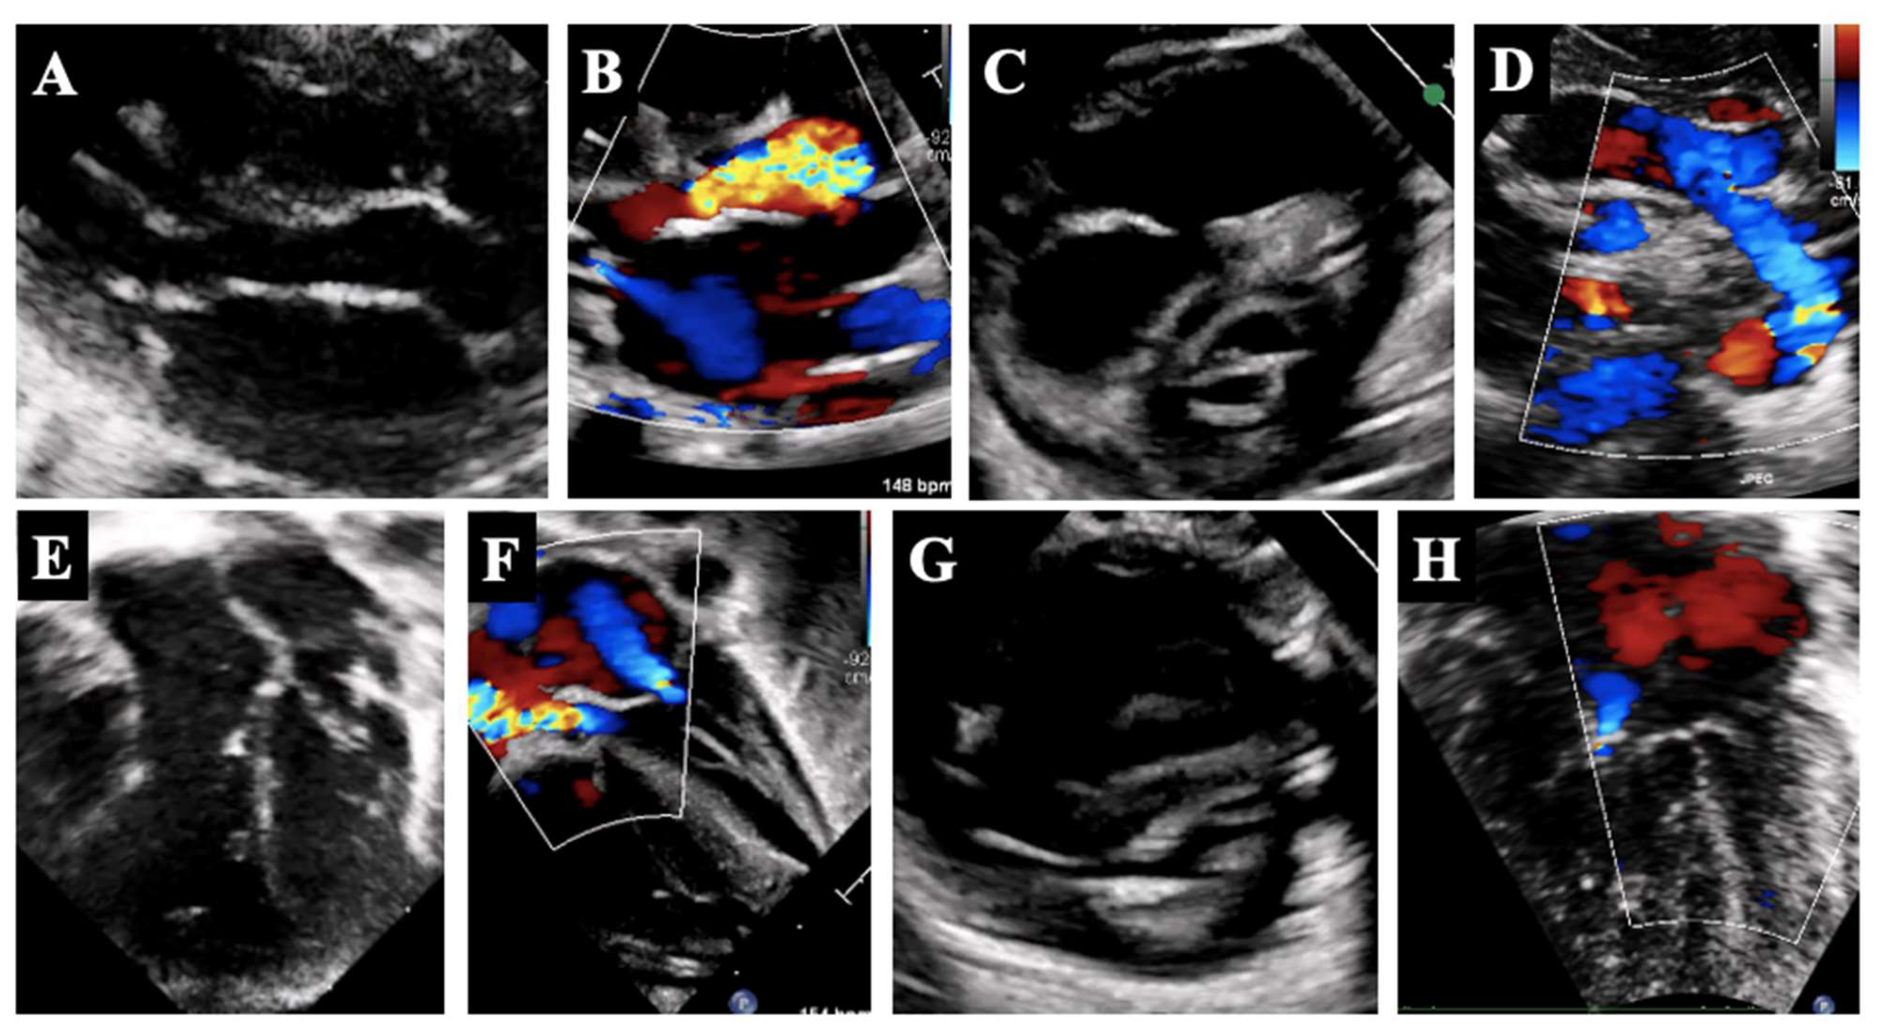

3. Borderline Left Ventricle: Predictors of Biventricular Repair

4. Borderline Right Ventricle: Predictors of Biventricular Repair

5.1. Borderline Left Ventricle

5.2. Borderline Right Ventricle